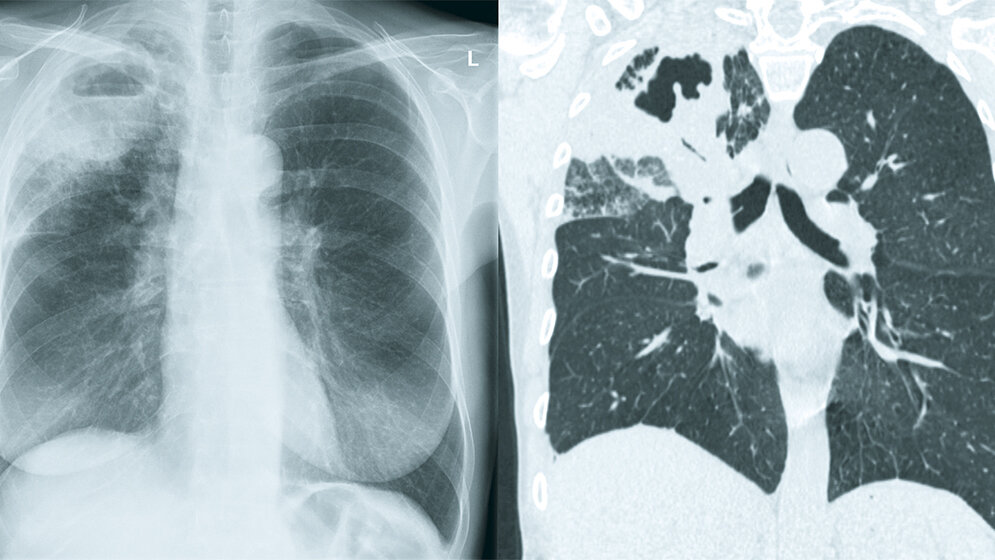

Bei der Tuberkulose-Infektion wird zwischen der primären Tuberkulose bei Erstkontakt und der postprimären Tuberkulose bei Reinfektion oder Reaktivierung unterschieden. Während die primäre Tuberkulose häufig selbstlimitierend ist und mit verkalkten Granulomen ausheilt, zeigt die postprimäre Tuberkulose häufig einen schweren Verlauf mit Kavernenbildungen insbesondere in den Oberlappen. Multiple pulmonale Noduli zeigen sich im Falle einer miliaren oder endobronchialen Aussaat und können hinweisgebend auf eine offene Tuberkulose sein. Auch wenn die Bildgebung nicht sehr spezifisch ist, kann sie dennoch Hinweise für oder gegen eine Tuberkulose-Infektion und mögliche Komplikationen wie beispielsweise eine offene Infektion geben.